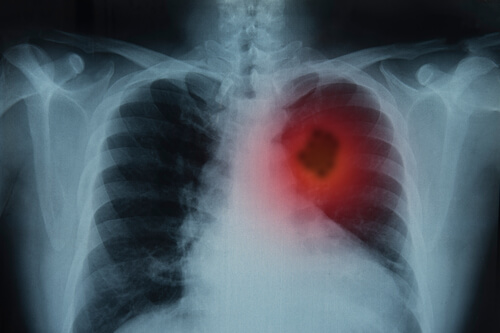

Si les signes persistent au-delà de trois semaines, il est indispensable que le patient consulte un médecin afin de réaliser une radiographie du thorax.

Ensuite, une fois les résultats présents, le médecin étudiera minutieusement le dossier, fera un examen physique et d’autres examens en laboratoire.

- Images. Il s’agit d’un procédé qui permet de capturer les zones internes du corps.